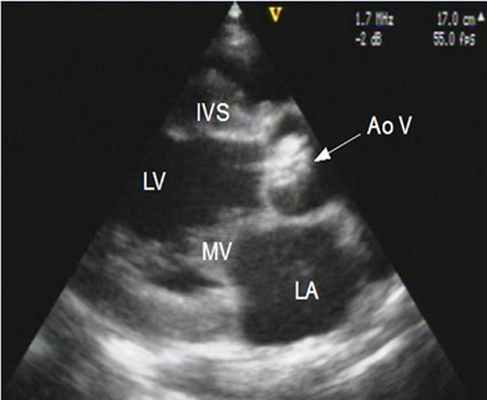

4. Эхокардиография (УЗИ-сердца) - является основным методом диагностики и оценки прогноза больных с аортальным стенозом. При этом возможна визуализация структур корня аорты и выносящего тракта левого желудочка, оценка подвижности створок и их состояния, определение локализации стеноза.

- ЭхоКГ. ЭХОКГ позволяет определить: структуру клапана (двустворчатый клапан, утолщение створок, фиброз, кальциноз, вегетации), характер его движения (подвижность створок, степень открытия) и площадь отверстия; изменения корня аорты (постстенотическая дилатация), объем левого желудочка, выраженность гипертрофии левого желудочка, нарушения локальной сократимости левого желудочка (указывающие на ИБС), ФВ, объем левого предсердия, состояние других клапанов. Доплеровское исследование позволяет с высокой точностью определить градиент давления между аортой и левым желудочком.